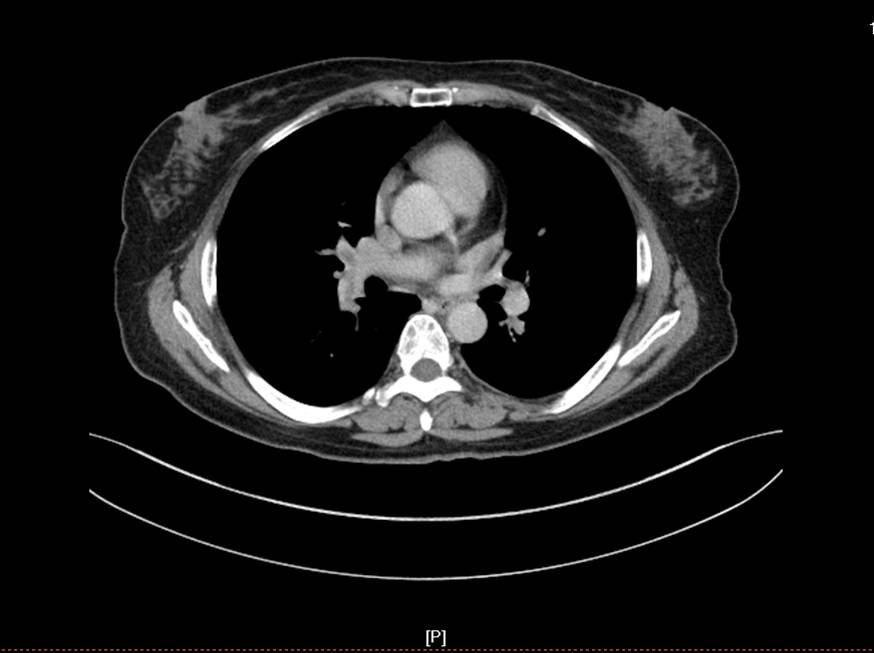

患者女性,52岁,因右膝关节疼痛2月为主诉入院。入院根据病史、查体和X线片诊断为右膝骨关节炎,经常规入院检查,未发现手术禁忌症,在硬膜外麻醉下行关节镜清理手术。术中应用止血带止血,手术过程顺利,手术时间为35分钟。术后给予弹力绷带包扎右下肢,术后第一天即嘱病人下地活动,疼痛较术前明显好转。术后给予了抗生素等药物,但未应用抗凝药物。术后第三天,患者出现右下肢肿胀、胸痛、呼吸困难,经行下肢超声和肺CT检查,结合血气分析等指标,呼吸科诊断为右下肢深静脉血栓形成,肺栓塞,转入呼吸科治疗。经溶栓、抗凝、支持等治疗2周后,病情痊愈出院。出院后继续服用华法林,定期检查凝血功能,维持INR值在1.5-1.5。

肺CT